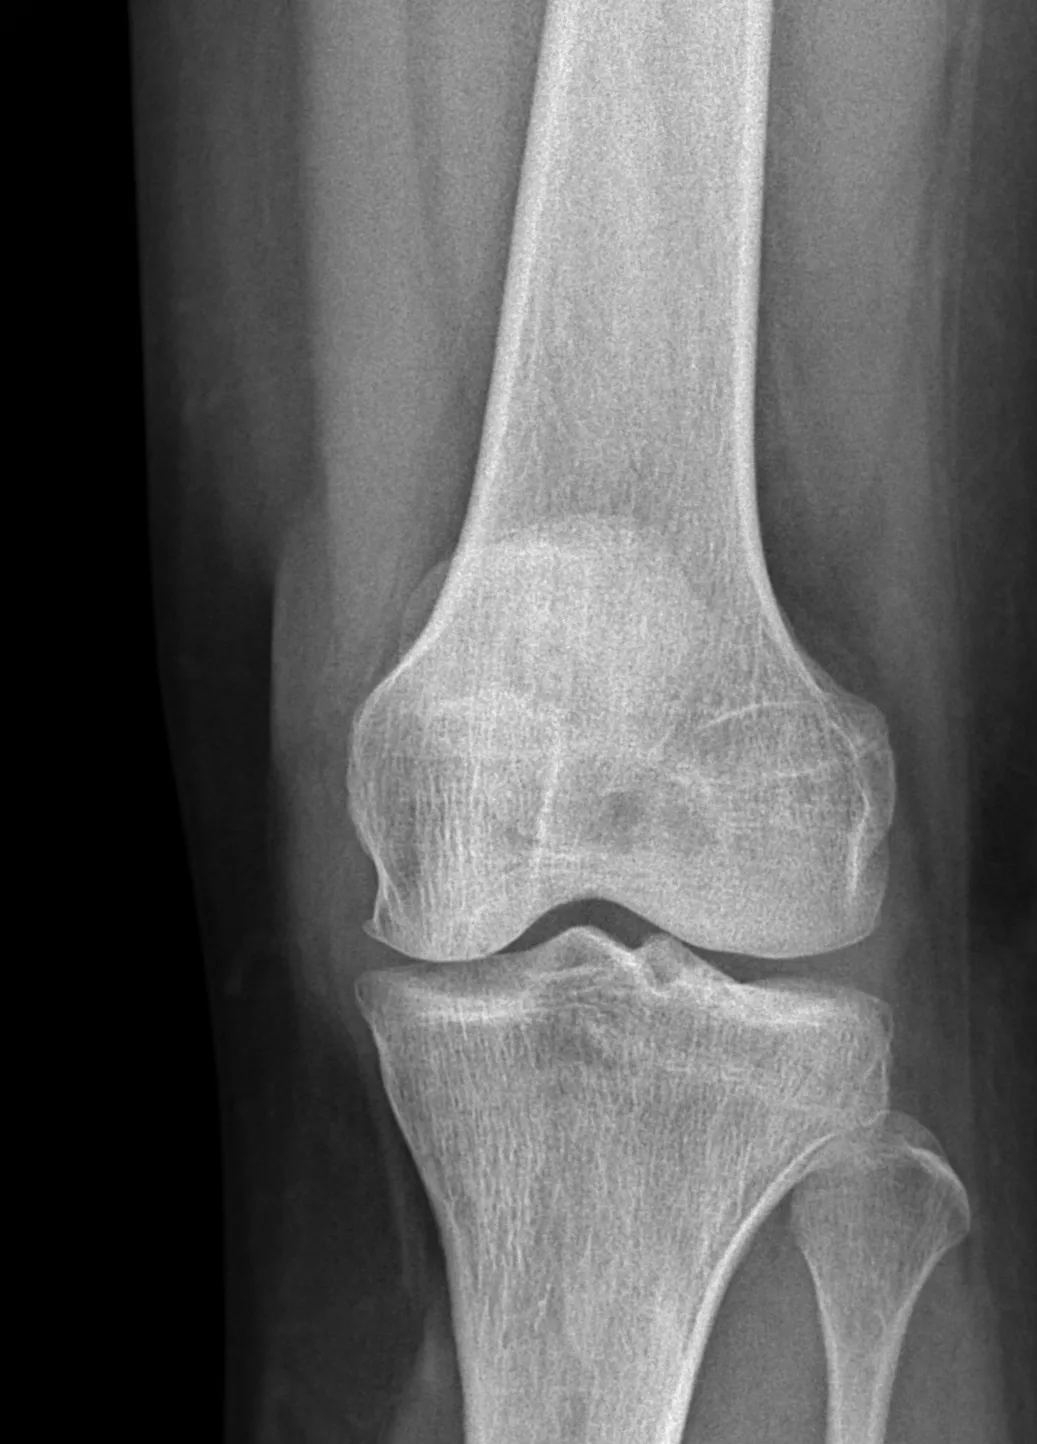

- X-rays to assess bone development and identify any discrepancies in leg length or deformities in the foot or ankle.